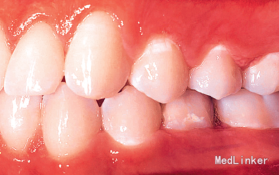

诊断:35牙缺失,牙列不齐 治疗:排齐整平上下牙列,对滞留的乳磨牙处理如下:因乳磨牙宽大,较正常前磨牙近远中径大很多,正畸治疗过程中逐次给乳磨牙减径后树脂修复参与正畸治疗,使减径树脂修复后的乳磨牙宽度为以后修复的前磨牙宽度一致。减径后的间隙留作牙列内其他牙齿的排齐。

2年正畸治疗结束后,乳磨牙仍在。一年以后,患者18岁成年,拔除乳磨牙,植入植体,半年后套冠,效果很好,患者满意。有些先天缺失第二前磨牙的患者,若第二乳磨牙比较健康,可以减径后树脂修复参与正畸治疗,这样有保存骨量,维持牙弓间隙,保持与对合牙功能接触以免对合牙伸长的作用。骨量的保存利于植体的植入。